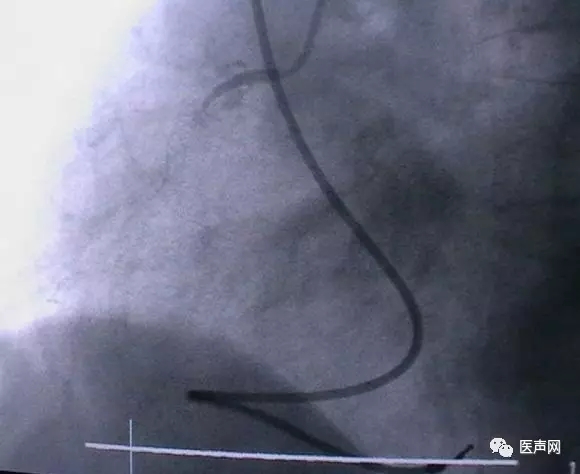

病例2:RCA 支架术后,近端CTO

CAG:RCA 支架术后,近端至远端支架,近端慢性闭塞病变(CTO)(下图所示)

手术经过:AL1.5导引导管,然后换AL2.0导引导管,在微导管支撑下,用硬导丝通过病变,直径1.25mm球囊至远端,远端有夹层,重至真腔,

但近端不确定是否真 腔,2.0mm CTO球囊可至RCA中段,导引导管弹出,重新进入,但近端可能是假 腔,终止手术,下次再试。

近端导丝在支架轮廓外侧

有3个Mark标记者为微导管,微导管可达RCA远段,但不一定在支架内走行。

· 导引导丝虽然在支架网眼外穿行,但球囊可以无阻力穿过,这不一定是真腔。导丝可能走在支架网眼与管壁之间,球囊不能扩!

· 即使导丝穿出支架网眼,但球囊可以无阻力穿过网眼。扩张时一定慎重!

· 做CTO时导丝可能从真腔-假腔-再到真腔。